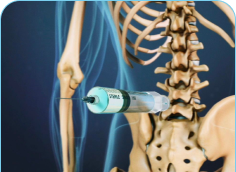

Radiofrequency Ablation may be used in cervical, thoracic, and lumbar spine. It can also be used in the sacroiliac joint and peripheral nerves, where the procedure is employed to reduce pain from the arthritic joints. Radiofrequency Ablation is a technique that employs heat to disable the pain-transmitting nerves in the spine.

The procedure is very safe and is only used on sensory nerves that transmit pain impulses. There is no risk of paralysis or weakness from this procedure. Radiofrequency Ablation uses heat to disable the pain-transmitting nerves in the spine. The process is analogous to microwave ovens that use microwave energy to heat food. Radiofrequency Energy is transmitted to the tip of a needle where it is converted to heat, which is applied directly to the nerve fibers. Once the nerves undergo this heat treatment, they slowly stop transmitting pain.